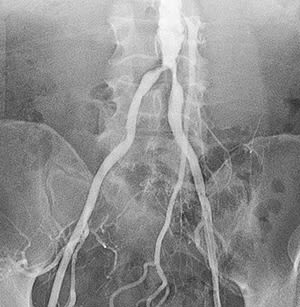

Peripheral angiography is a test that uses X-ray and dye (contrast material) to map the blood vessels (arteries) in your lower body, legs, and arms. This map can show where blood flow may be blocked.

- Contrast dye is injected into the catheter to confirm position. You may feel warmth or pressure in your legs and back. You lie still as X-rays are taken. The catheter is then taken out.